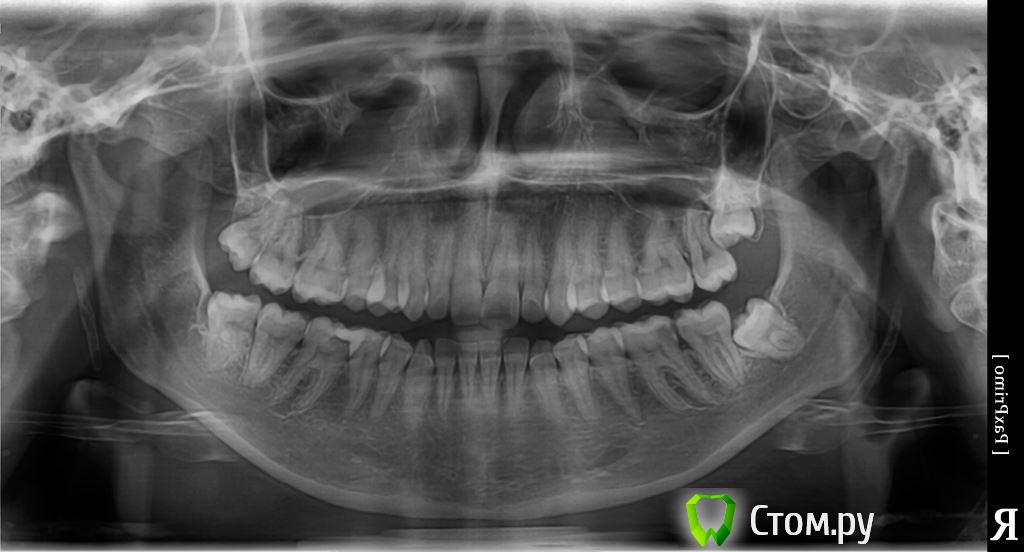

Панорамный снимок. Ваше мнение.

Впервые обратилась к стоматологу (27 лет) с болью в зубе. Сделали панорамный снимок. В итоге: лечили пульпит с удалением нерва снизу 6, 4 -канальный оказался (на снимке там временная пломба и мышьяк).

Просьба к специалистам, можно по снимку определить в каких еще зубах кариес?

Нужно ли удалять "зубы мудрости", т.к. они растут криво (их пока не видно, под десной)?

Как можно избавиться от "капюшона", на крайних зубах (которые уже вылезли)?

Проф. гигиена + обучение (нужно пользоваться зубной нитью)

Консультация ортодонта

8ки удалять

Лечение 27,37,36, 45,46,47 - скорее всего